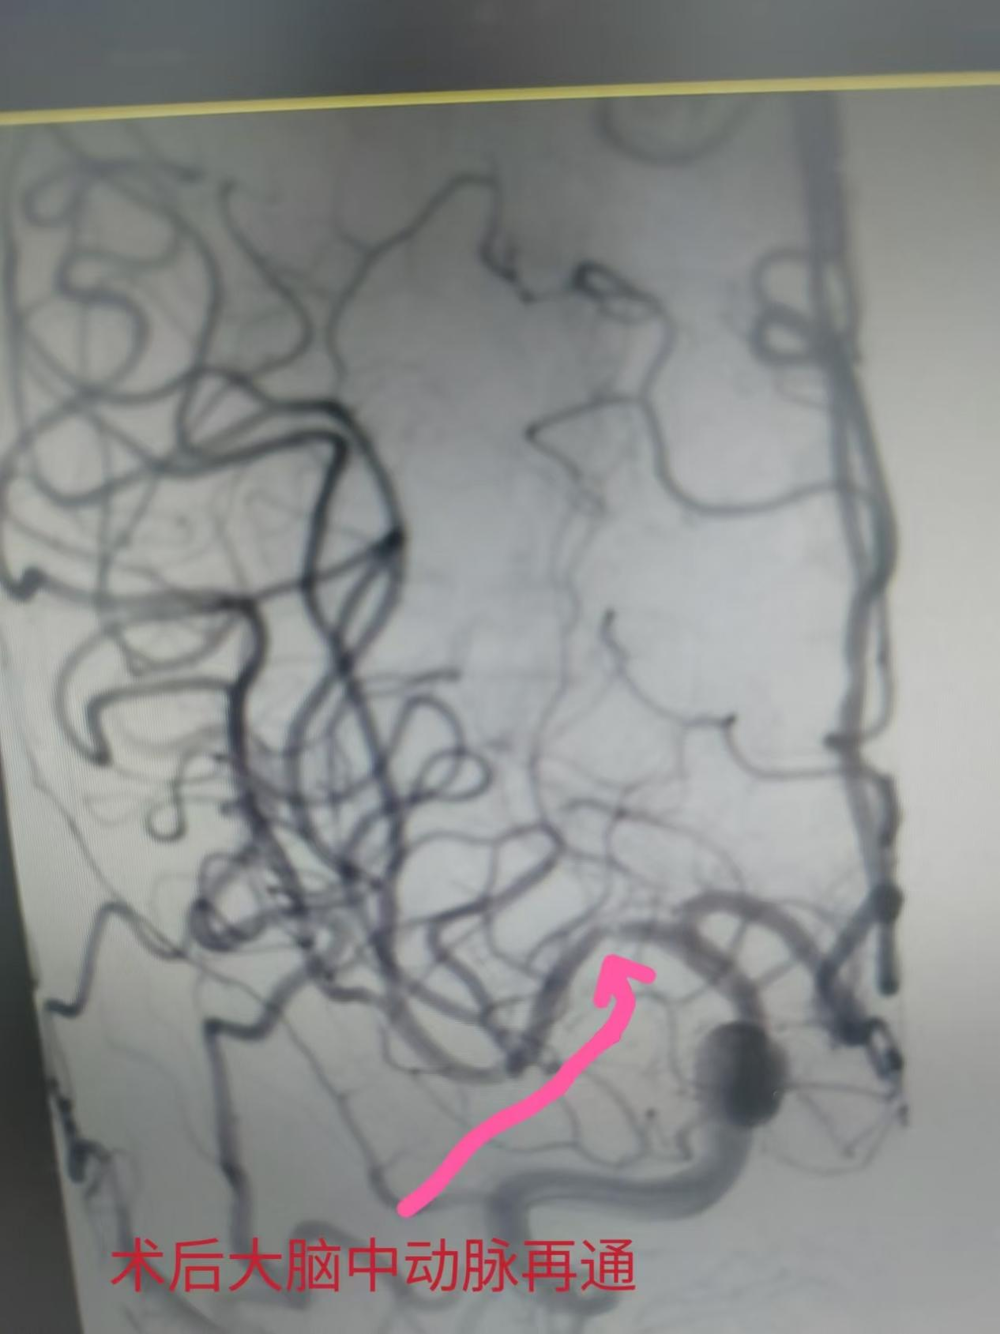

术后大脑中动脉再通

神经内科胡华林主任及其介入团队快速制定手术方案。通过介入取栓加脑血管球囊扩张成形手术,50分钟开通了闭塞的右侧大脑中动脉,梁先生的右侧大脑中动脉成功恢复了血流再通。手术非常顺利,梁先生术后言语恢复清晰,能够自由下床活动,日常生活能自理。胡华林主任针对梁先生基础疾病及时调整用药,并叮嘱规律服药和返院复查等相关事宜,术后1周后梁先生顺利出院。